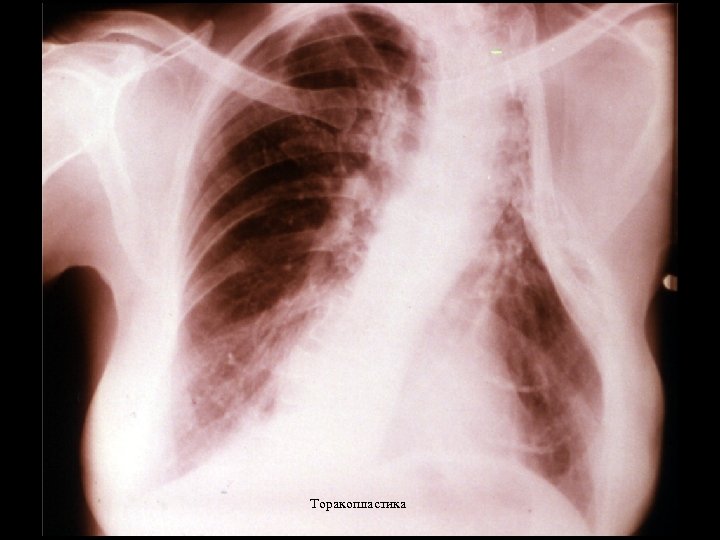

Постельный режим (2) • Температуру измеряют 6 раз в день • Даются строгие предписания по режиму питания • Пациенты проходят лечение в санатории длительностью от нескольких месяцев до нескольких лет • После 1910 г. внедряется лечение методом пневмоторакса • Позже начинают применять торакопластику и парафиновые пломбы

Торакопластика